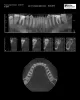

Зуба мудрости во рту нет, десна бледно розовая, во рту проблем нет. Но появились боли, уже месяц в области 6 и 7 зуба внизу справа, то верхние зубы справа (проверила, они здоровы). Также боли у уха, под глазом, щека, в шее от мочки и вниз. Обошла всех врачей, никто не знает отчего. Думала на зуб мудрости, но говорят, что с ним можно жить всю жизнь т.к. он ретинированный и ничем не грозит. Уезжаю на море, на все лето, боюсь, чтобы не заболели зубы от жары. Направила Вам снимки: первый снимок годовалой давности, далее КТ и ортопант - они сделаны только сейчас.

Есть ли какие то изменения на снимках? Есть ли какие то изменения с зубом мудрости? Можно ли данный зуб мудрости не удалять?

Рекомендуем вам обратиться на прием к стоматологу-хирургу. Восьмой зуб расположен таким образом, что никогда полноценно в зубной ряд не прорежется. Но так как он сохраняет тенденцию к прорезыванию, то будет вызывать боль, сдавливая окружающие ткани, а так же гипертонус мышц. Как правило, такие зубы рекомендуется удалить.